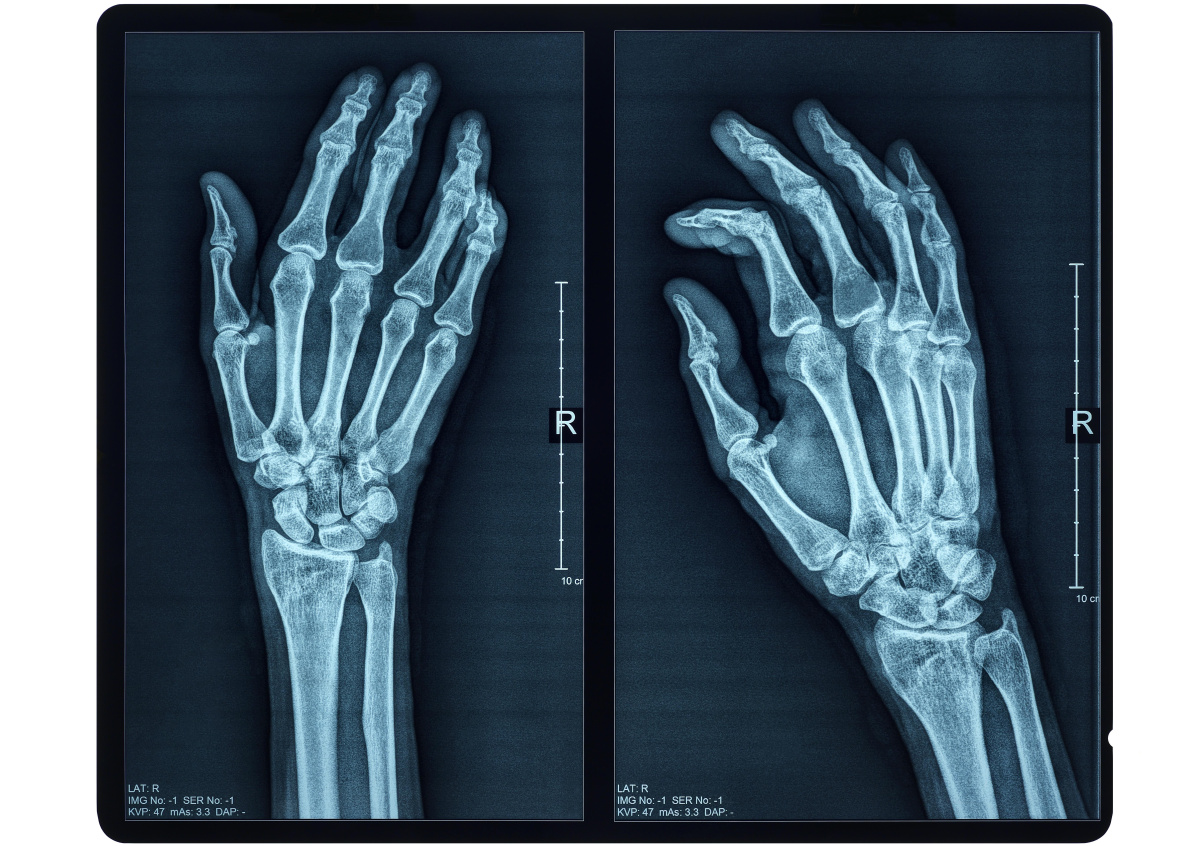

Фото: Simon Belcher/imageBROKER.com/Global Look Press

Методику восстановления костей на 3D-принтере с минимальным отторжением разработали австралийские учёные. Они намерены выращивать кости прямо в теле человека.

В новой технологии будут использовать настоящие клетки организма и 3D-принтер. Для этого создаётся 3D-модель кости человека, которая помещается в принтер. Устройство уже внутри организма создаёт естественную кость. Как утверждают учёные, это вызывает минимальное количество отторжений.

Это первый пример использования керамических материалов, эмулирующих кости с живыми клетками. Новая технология открывает возможность печати костей человека прямо в организме, — заявили учёные.